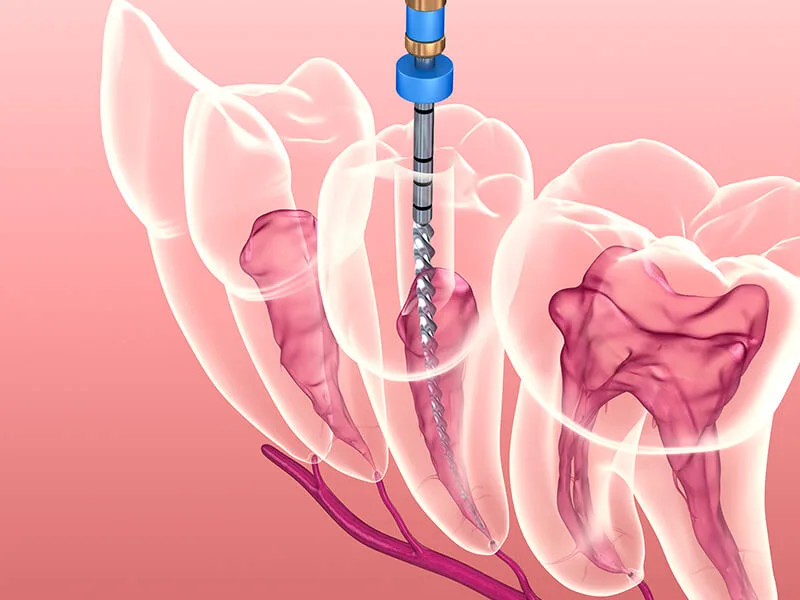

Na primeira visita, o paciente passa por uma avaliação detalhada para identificar a condição real da polpa dentária. O cirurgião discutirá as opções para preservar o dente natural, focando na eliminação total de infecções.